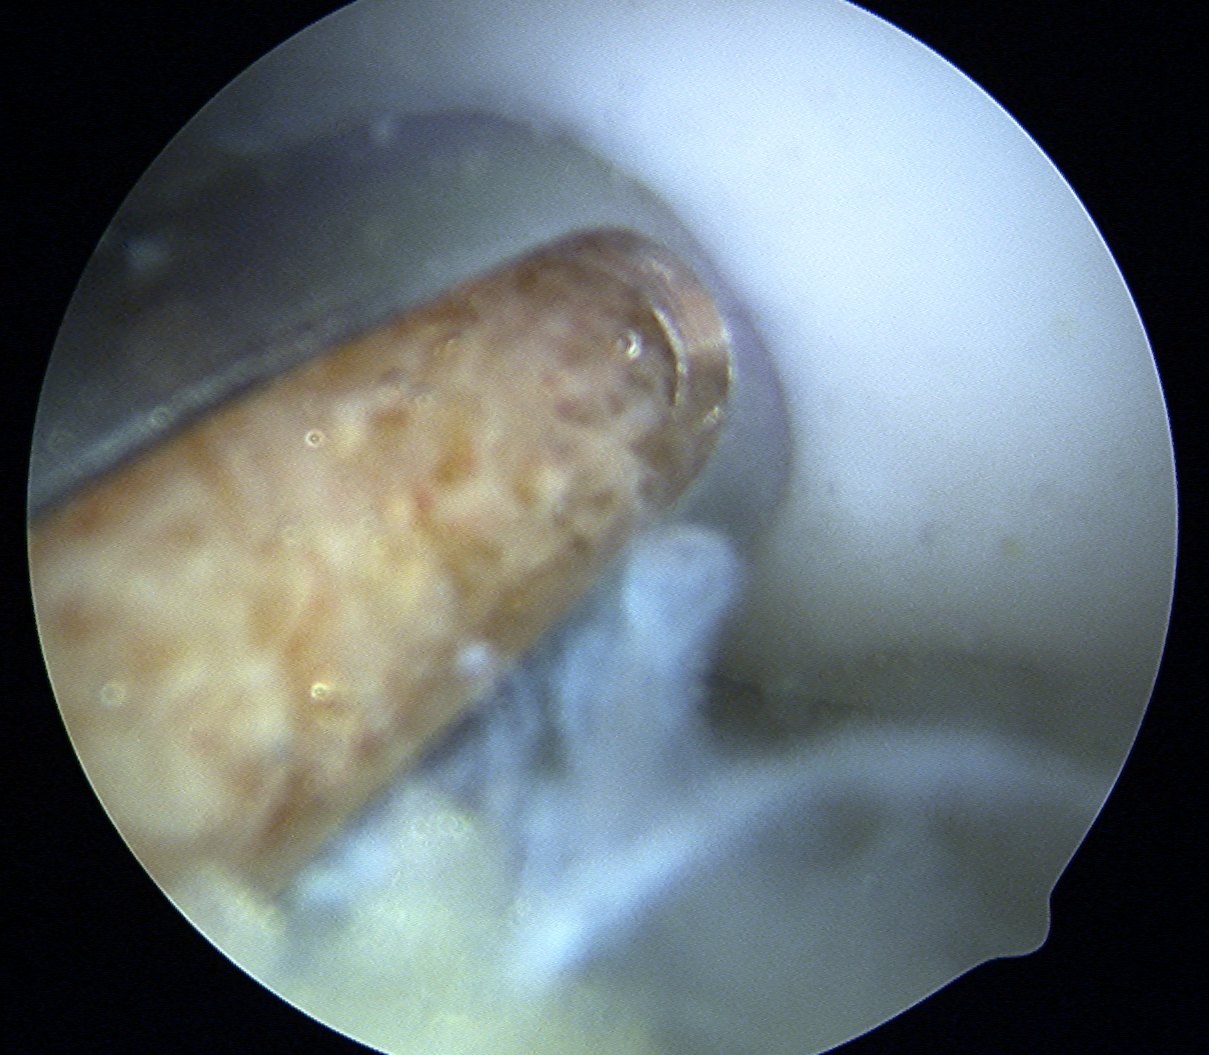

Debride base of OCD and reduce

Drill site of mosaicplasty with 4.5 mm drill

- overdrill 2 - 4 mm

- do not want to leave plug proud

- impossible to sink further or remove